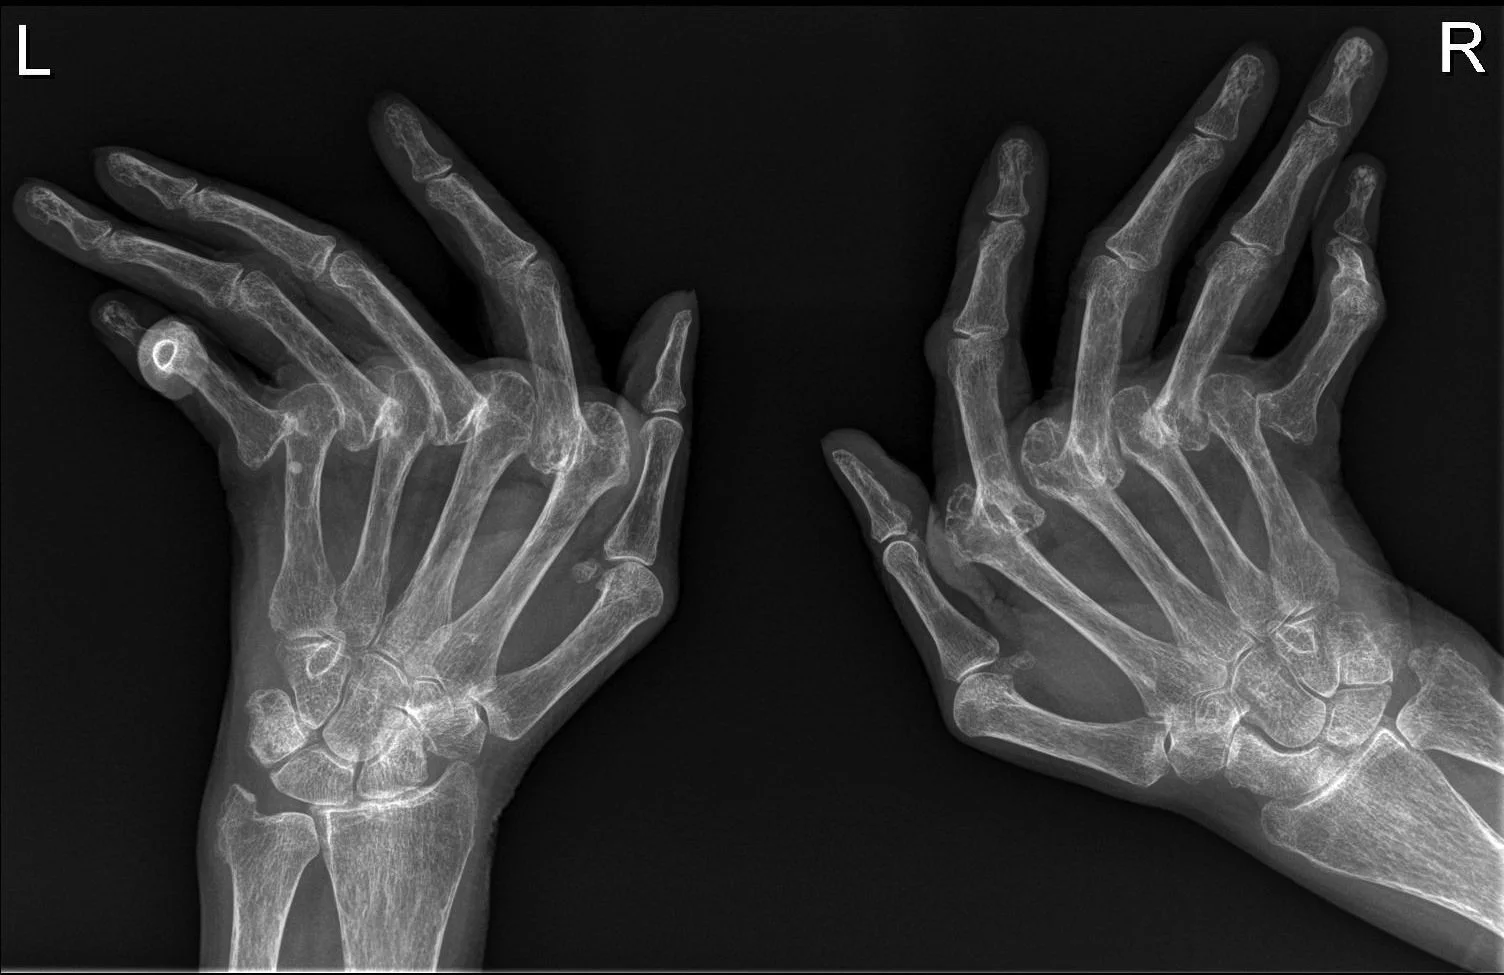

As you can see in the x-ray above, RA has the potential to severely damage joints to the point that they become deformed. My mom, who has osteoarthritis in her hands, describes my aunt's RA as the "crippling" kind of arthritis due to possible deformation that can occur with this disease.

Rheumatoid Arthritis is particularly unfortunate because it's an autoimmune inflammatory arthritis. That means that the immune system, (the body's natural defense system against infection and sickness), goes haywire and starts attacking joints in your body. Typically, RA likes to attack small joints in the hands, wrists, ankles, and feet, but it will also go after the knee and can in some instances be seen in the hips as well. RA prefers small joints though, so those locations are uncommon.